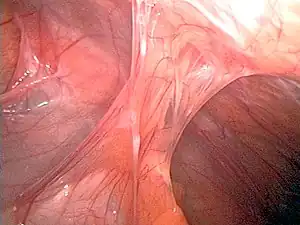

| Adhesions formed following appendectomy |

Adhesions are fibrous bands that form between tissues and organs,[1] often as a result of injury during surgery. They may be thought of as internal scar tissue that connects tissues not normally connected.